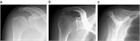

1. 急性の石灰沈着性滑液包炎は、腱板内に沈着した石灰が肩峰下滑液包へ流出して発生する結晶性滑液包炎である。突然発症する例が多い。

1. 腱板内に沈着した石灰が大きくなり、慢性化してインピンジメント症状や関節拘縮を引き起こすこともある。

1. 無症候性の石灰沈着症の発生率は人口の2.7~20%で、30~50歳に好発する。有症状の沈着症は50歳前後であり、女性(男女比は3:2)と棘上筋腱に多い。